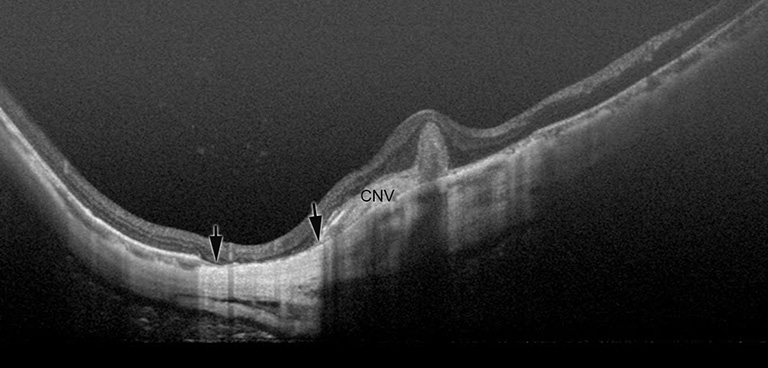

Myopic CNV and CNV-related macular atrophy (Figures 5,6)

figure5

figure6

Myopic CNV is a major sight threatening complication of PM. It is the commonest cause of CNV in individuals aged below 50 years, and the second commonest cause of CNV overall (35,36). Myopic CNV tends to be small and thus about 20% of them was extrafoveal (37). Most of them are type II CNV, above the RPE. In natural course as well as after treatment, myopic CNV goes through three phases; active phase, scar phase, and atrophic phase (also known as myopic CNV-related macular atrophy) (Figure 7).

However, it is not fully clarified whether anti-VEGF treatments are effective for late complications occurring around the scarred myopic CNV; which is CNV-related macular atrophy. Recent study using swept-source OCT by Ohno-Matsui et al. (41) showed that CNV-related macular atrophy was also an enlarged hole of BM around the CNV (Figure 5). To improve the long-term outcome of anti-VEGF therapies for myopic CNV, the prevention of BM hole enlargement around the CNV is necessary.